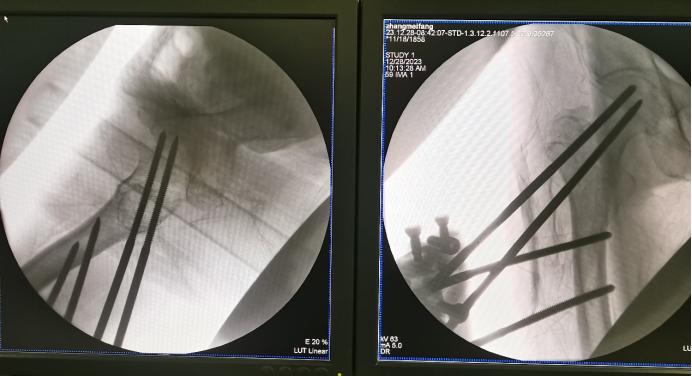

在完善相关检查,手术时机成熟后,海军军医大学第三附属医院创伤骨科手术团队为患者在局麻下行右股骨粗隆间骨折闭合复位外固定术+右桡骨远端骨折闭合复位克氏针外固定术+石膏固定术,手术历时不到1小时,术中显性出血约10毫升,骨折得到了良好复位。

股骨粗隆间骨折术中透视图像

桡骨远端骨折术中透视图像